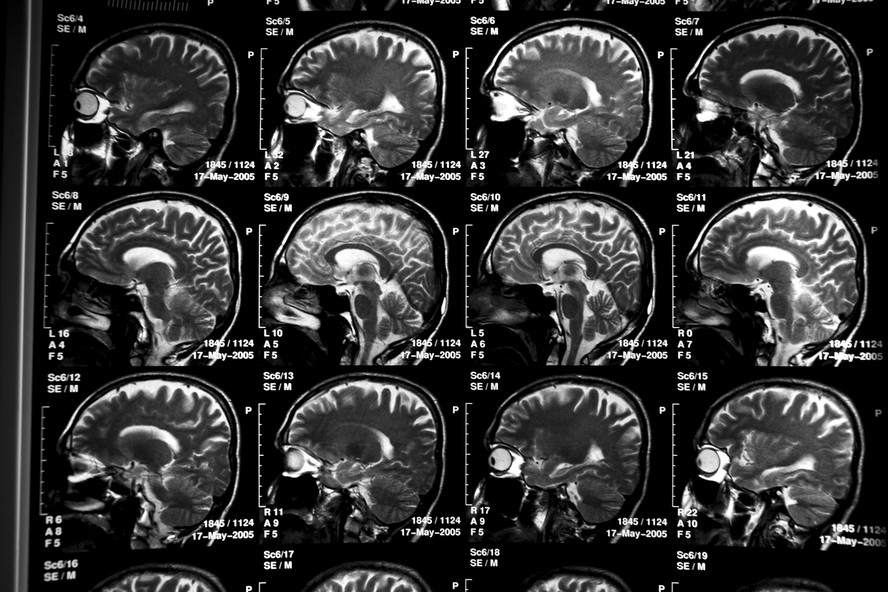

Exames de cérebro de paciente com Alzheimer. — Foto: Todd Heisler/The New York Times